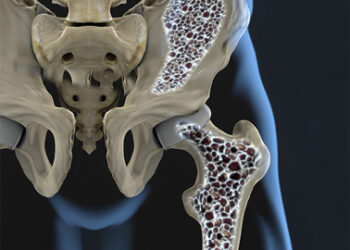

Read moreBiotecnología y osteoporosis: avances en Baja California Sur para combatir esta “enfermedad silenciosa”

La osteoporosis es una condición que afecta la estructura ósea de manera progresiva y silenciosa, aumentando el riesgo de fracturas...